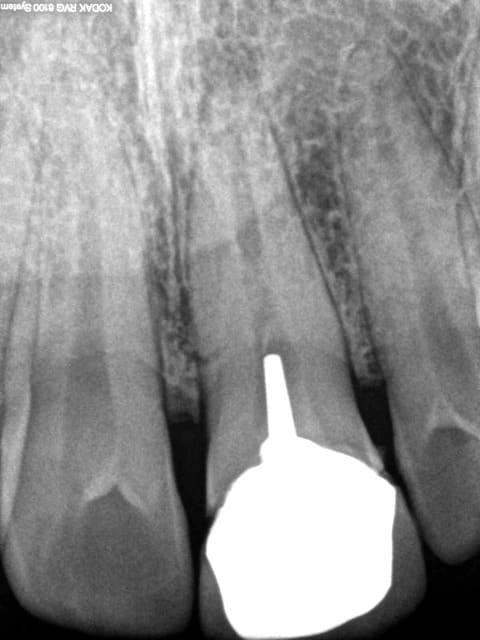

Tiens un cas s'approchant du tiens Chicot...comme je suis mauvais en Endo, j'essaye d'en faire le moins possible.

J'ai gardé vivant ce que je pouvais.

Le cas à 3 ans... RAS, j'ai vu la patiente il y a 2 mois.